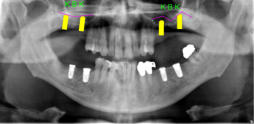

Beispiele für komplexe implantologische Versorgungen aus unserer Gemeinschaftspraxis

(Planung / Endversorgung -- als Röntgenaufnahmen)

C1

C2

C3